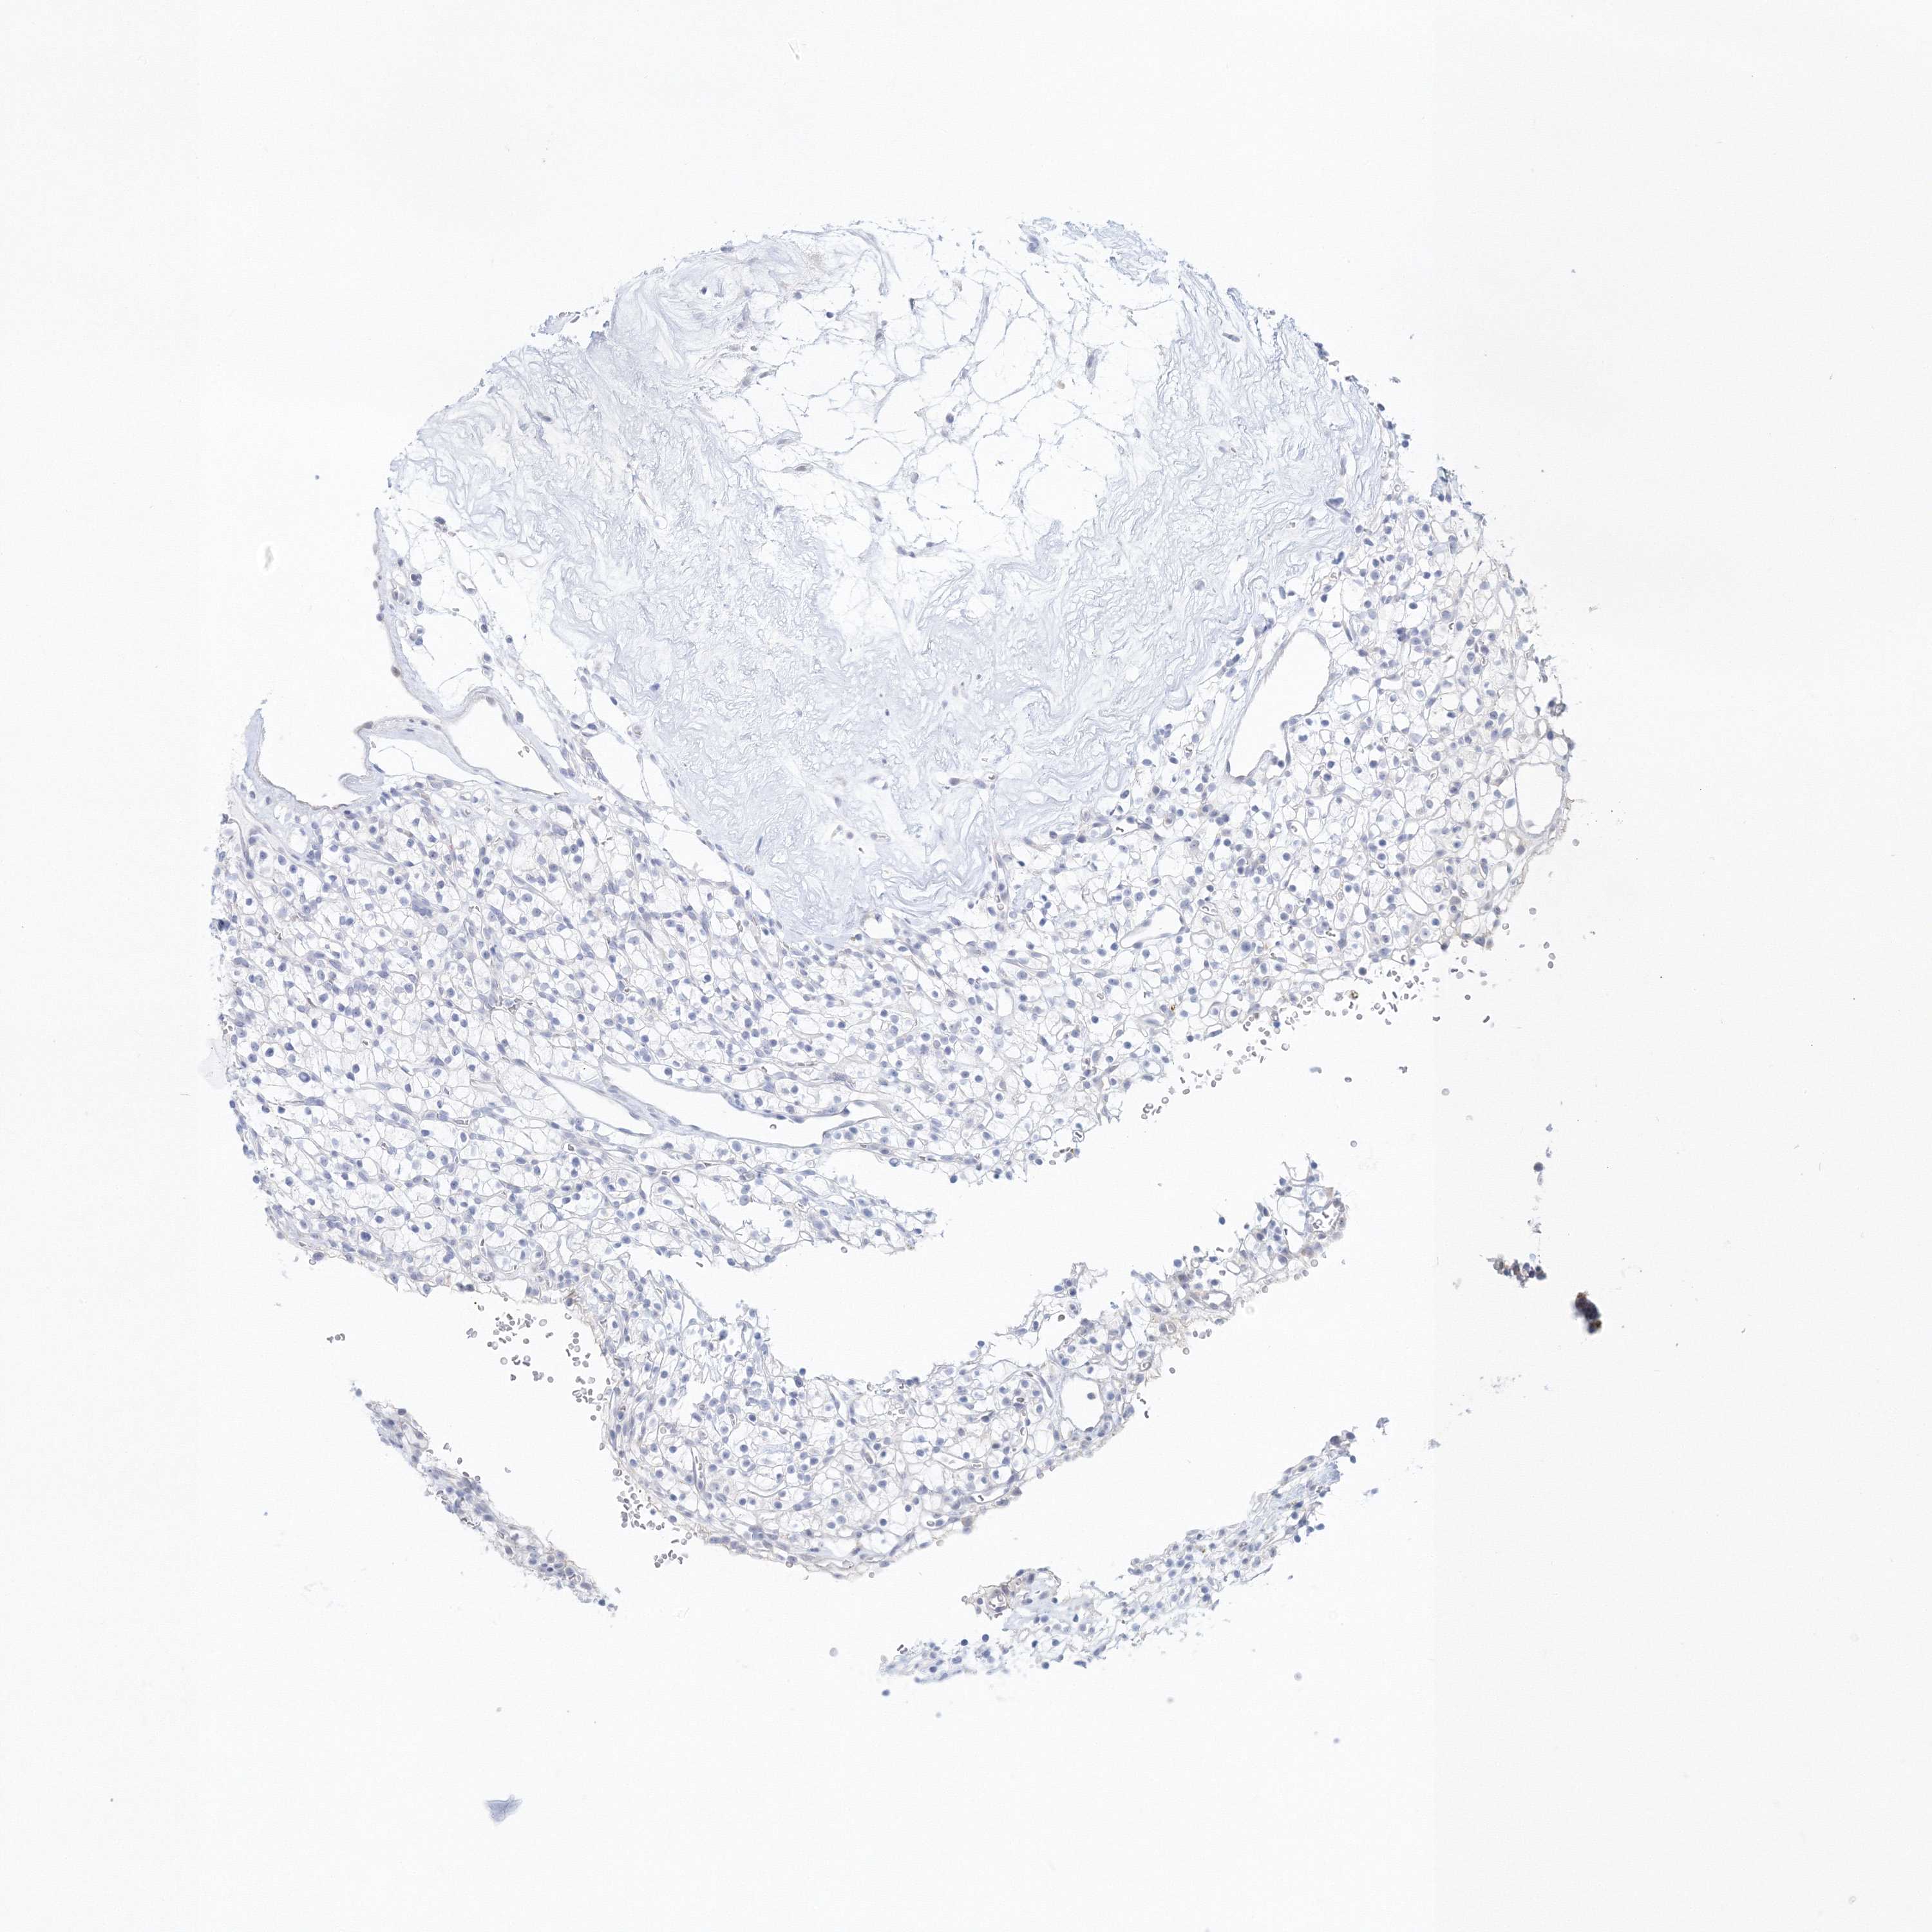

KIDNEY RENAL CLEAR CELL CARCINOMA (VALIDATION) - Interactive survival scatter ploti

The Survival Scatter plot shows the clinical status (i.e. dead or alive) for all individuals in the patient cohort, based on the same data that underlies the corresponding Kaplan-Meier plots. Patients that are alive at last time for follow-up are shown in blue and patients who have died during the study are shown in red.

The x-axis shows the expression levels (FPKM) of the investigated gene in the tumor tissue at the time of diagnosis. The y-axis shows the follow-up time after diagnosis (years). Both axes are complimented with kernel density curves demonstrating the data density over the axes. The top density plot shows the expression levels (FPKM) distribution among dead (red) and alive patients (blue). The right density plot shows the data density of the survived years of dead patients with high and low expression levels respectively, stratified using the cutoff indicated by the vertical dashed line through the Survival Scatter plot. This cutoff is automatically defined based on the FPKM cutoff that minimizes the p-score. The cutoff can be changed by dragging the vertical line or by entering a cutoff value in the square labeled "Current cut-off".

Under the Survival Scatter plot the p-score landscape (black curve; left axis) is shown together with dead median separation (red curve; right axis). Dead median separation is the difference in median mRNA expression between patients who have died with high and low expression, respectively. It is calculated as follows: median FPKM expression of dead patients with high expression - median FPKM expression of dead patients with low expression. This is intended to aid the user in visually exploring custom cutoffs and the associated p-scores and dead median separation.

Individual patient data is displayed and can be filtered by clicking on one or more of the category buttons on the top of the page. Categories describing expression level and patient information include: high, low, alive, dead, female, male and tumor stages. The scale of the x-axis can be toggled between linear and log-scale by clicking on the "x log" button. Mouse-over function shows TCGA ID, patient information and mRNA expression (FPKM) for each patient.

& Survival analysisi

Kaplan-Meier plots summarize results from analysis of correlation between mRNA expression level and patient survival. Patients were divided based on level of expression into one of the two groups "low" (under cut off) or "high" (over cut off). X-axis shows time for survival (years) and y-axis shows the probability of survival, where 1.0 corresponds to 100 percent.

VSIG1 is not prognostic in Kidney Renal Clear Cell Carcinoma (validation)

: 3.72

Average pTPM 2.7

Number of samples 100